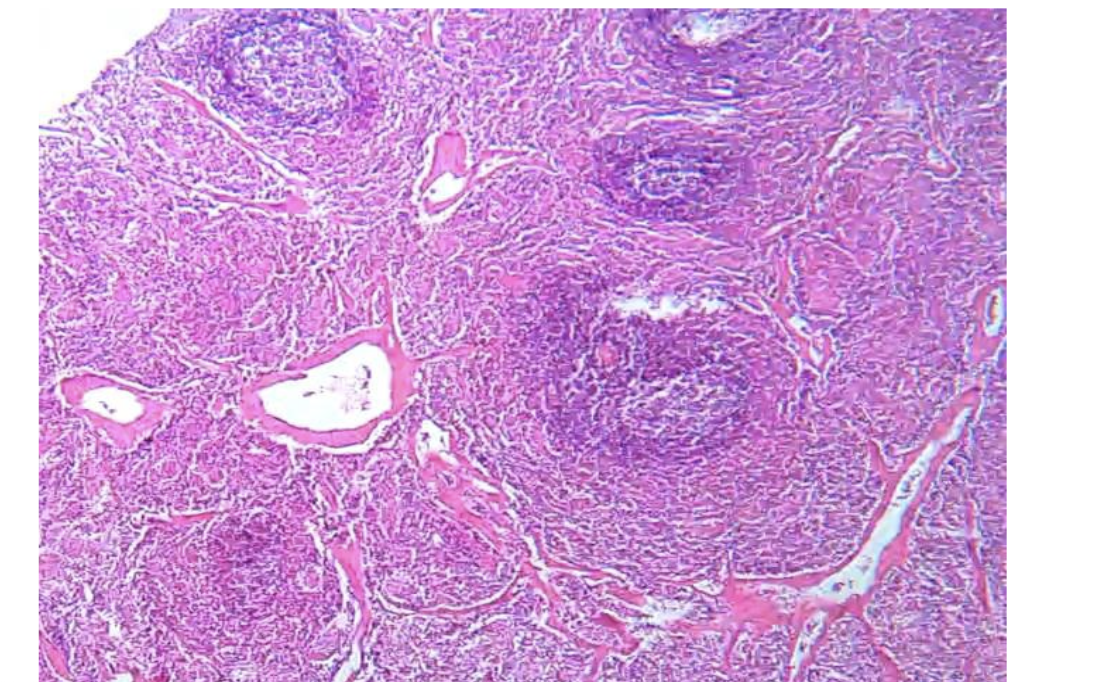

???

Lymph Node

Mention the points

of identification?

Outer cortex: cortical follicles & sinuses.

Inner medulla: medullary cords and sinuses.